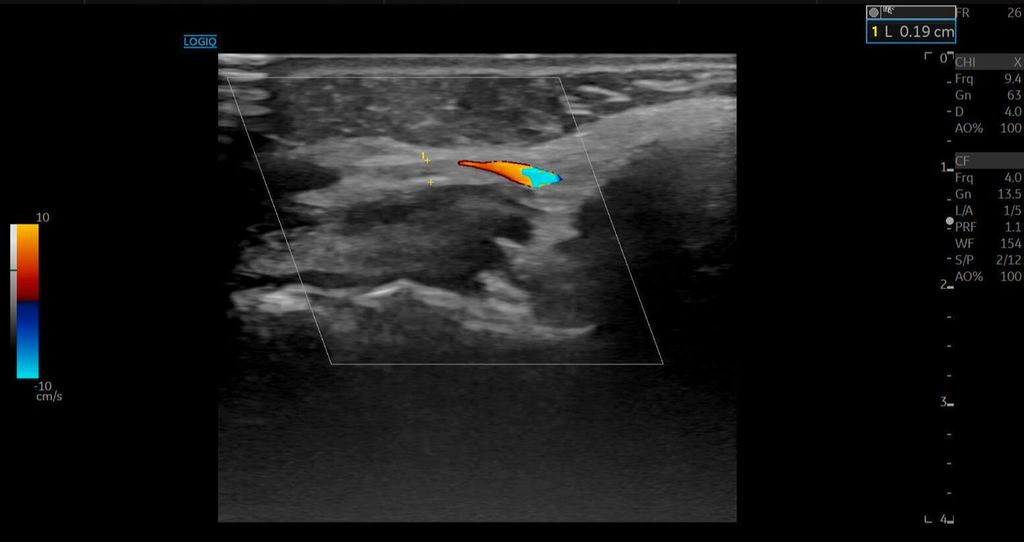

Die A. facialis imponierte beim Austritt im Bereich des Musculus masseter (oberhalb der Kieferlinie) vasospastisch mit einem maximalen Durchmesser von 1mm. Die abgeleitete systolische Spitzengeschwindigkeit betrug trotz der bestehenden Ischämie 20cm/s, ohne enddiastolische Komponente, was auf eine weitere periphere Vasokonstriktion hindeutete (Abb. 2 und 3).

Die Duplexsonografie ergab folgende Befunde (Abb. 5 und Abb. 6):

Der Durchmesser der A. angularis und A. facialis hatte sich nahezu verdoppelt.

Die systolische Spitzengeschwindigkeit (PSV) stieg von 20cm/s auf über 100cm/s.

Die enddiastolische Geschwindigkeit (EDV) betrug nun 20cm/s, was auf eine periphere Vasodilatation und eine Wiederherstellung der Makrozirkulation hindeutete (Abb. 7).